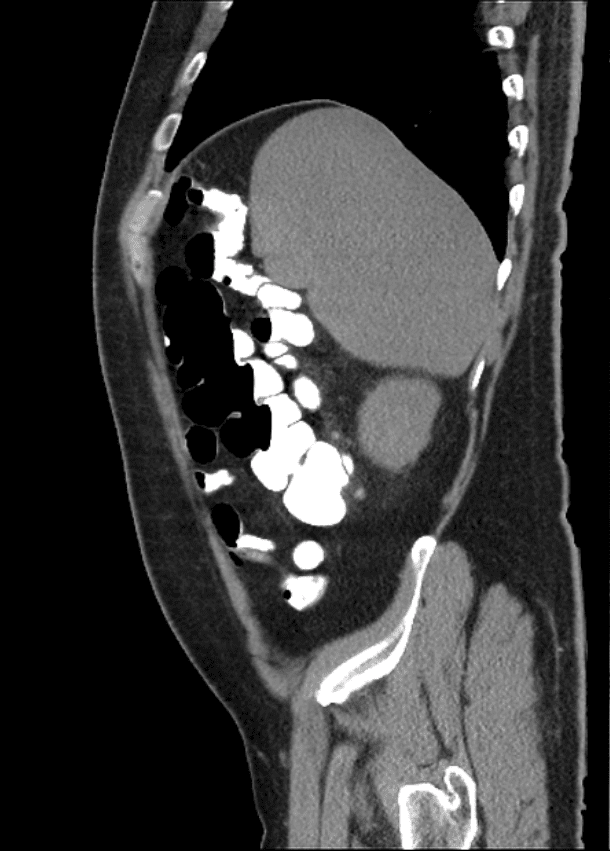

Chilaiditi

Chilaiditi - Ảnh 4

» Thông tin: Nam giới – 48 tuổi.

» Lâm sàng: Đau mạn sườn phải 1 tháng.